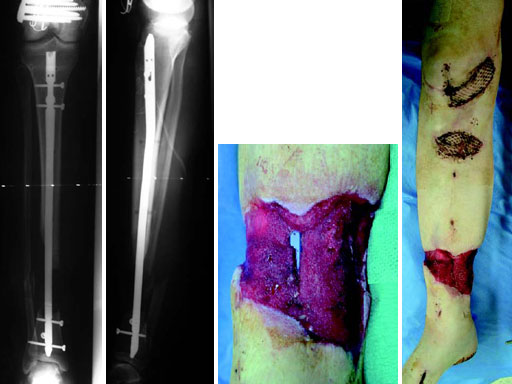

A 33-year-old female sustained a grade III open fracture of the right lower leg.

Case provided by Michael Raschke, Mnster, DE